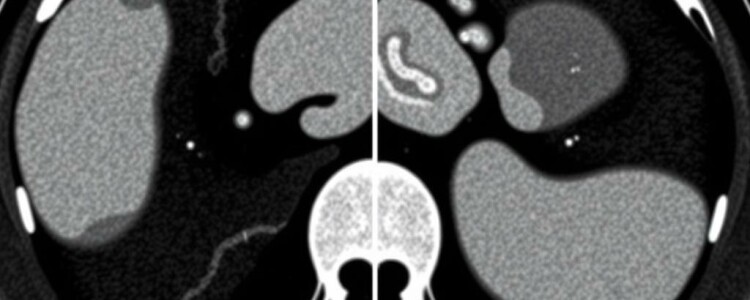

La tomografía computarizada ofrece imágenes transversales detalladas del abdomen que permiten ver el apéndice, su tamaño, la presencia de líquido, engrosamiento de la pared, y signos indirectos de inflamación o perforación. Antes de la adopción generalizada de la TC, el diagnóstico de apendicitis dependía en exceso de la exploración física, los síntomas y tablas de puntuación clínica. Eso llevaba a tasas de apendicectomías negativas (operar cuando el apéndice no está inflamado) y a retrasos diagnósticos peligrosos. Con la TC se redujo significativamente la incertidumbre, pero surgieron nuevos retos: interpretación dependiente del radiólogo, variabilidad entre observadores, y tiempos de espera en servicios saturados. Aquí es donde entra con fuerza la inteligencia artificial, no para sustituir la mirada experta, sino para estandarizar, acelerar y complementar la lectura de imágenes.

Las CNN son la columna vertebral de muchos avances en visión por computador. En el contexto de TC, las CNN 2D procesan cortes individuales, mientras que las CNN 3D procesan volúmenes completos, capturando relaciones espaciales en tres dimensiones. Para apendicitis, las CNN 3D tienden a ser más informativas porque preservan la anatomía volumétrica del apéndice y tejidos circundantes. Estas redes aprenden a distinguir tejidos inflamados, identificar colecciones y ver trayectos fistulosos sugerentes de perforación.

Dos tareas técnicas recurrentes son la segmentación (separar el apéndice y estructuras de interés del resto de la imagen) y la detección/classificación (decidir si hay apendicitis y su probabilidad). Para segmentación se usan U-Net y variantes 3D U-Net; para detección, arquitecturas basadas en CNN clásicas o modelos de clasificación más recientes. La segmentación también ayuda a medir el diámetro del apéndice y evaluar derrames periapendiculares de forma automatizada, ofreciendo métricas cuantitativas que refuerzan la interpretación clínica.